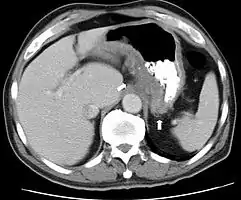

Endoscopic image of Crohn's colitis showing deep ulceration CT scan showing Crohn's disease in the fundus of the stomach

CT and MRI scans are useful for evaluating the small bowel with enteroclysis protocols.[138] They are also useful for looking for intra-abdominal complications of Crohn's disease, such as abscesses, small bowel obstructions, or fistulae.[139] Magnetic resonance imaging (MRI) is another option for imaging the small bowel as well as looking for complications, though it is more expensive and less readily available.[140] MRI techniques such as diffusion-weighted imaging and high-resolution imaging are more sensitive in detecting ulceration and inflammation compared to CT.[141][142]